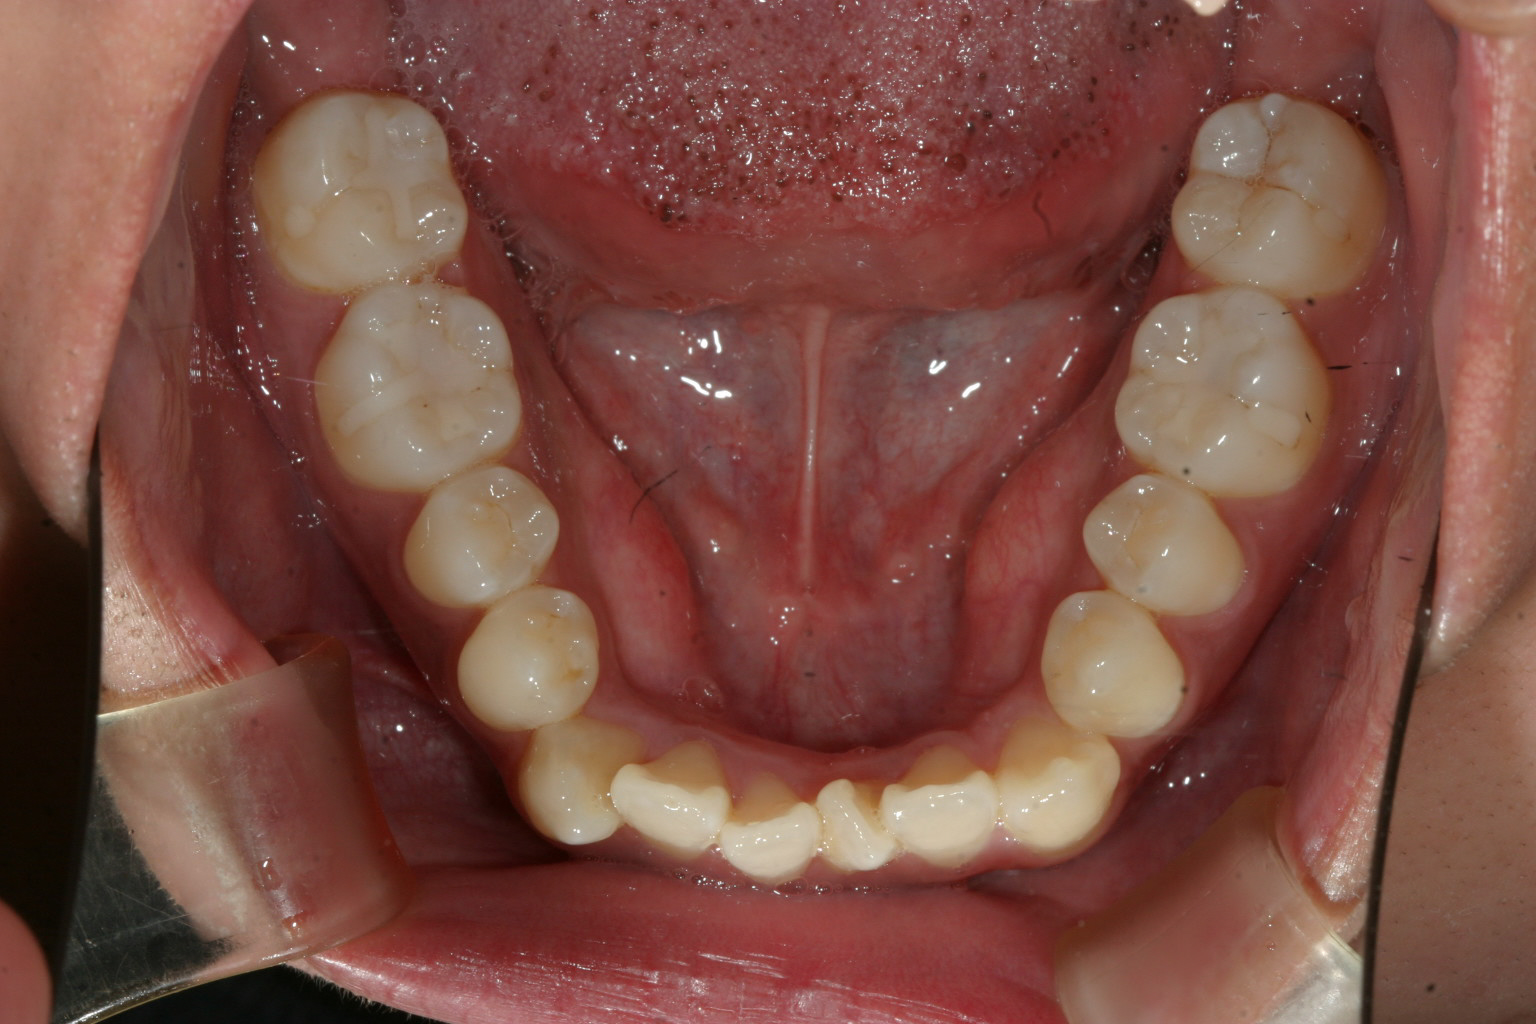

左の犬歯が完全にはじき出されています。

前歯部に叢生が見られます。